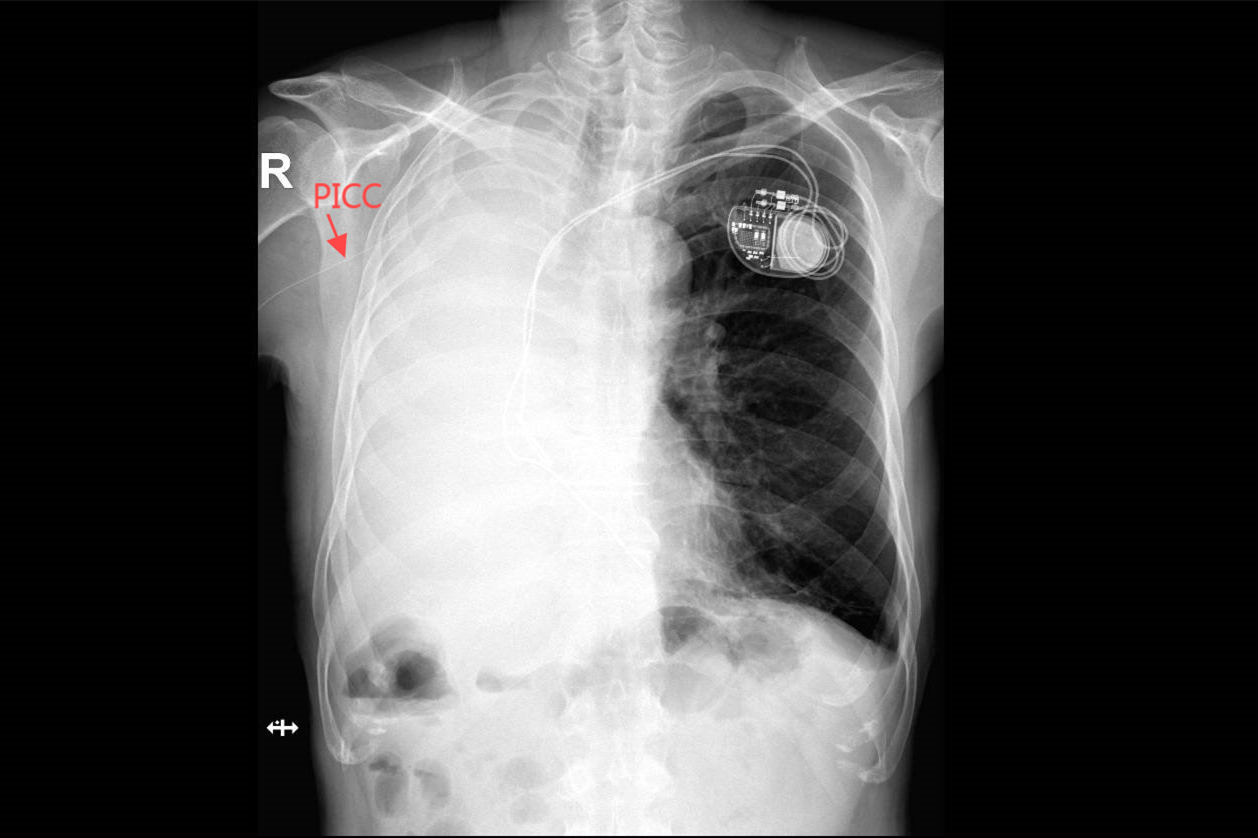

“患者外周血管条件极差,输注化疗药物以及脂肪乳、氯化钾等高渗性药物,极易使血管破坏或药物外渗,导致局部组织坏死。为了后期治疗的安全顺利进行,需要置入PICC导管。”南院肿瘤内二科护士长宫新玲介绍,为该患者置入PICC导管的难点在于,胸部CT显示心脏起搏器置于患者左侧锁骨下,两根电极导线经锁骨下静脉、头臂静脉、上腔静脉进入右心房和右心室。如果PICC导管从左手臂置入,其走行途径与心脏起搏器植入电极导线的走行途径大部分是相同的,这不仅会使穿刺部位的选择受限,还极易导致送管过程不顺畅。

为保障患者安全,置管过程中全程进行心电监护,并给予心理护理,缓解患者的紧张情绪。凭借丰富的临床经验以及前期的充分准备,PICC置管工作顺利完成,置管术后胸部正位片(DR)显示置管位置良好。在化疗过程中仍密切观察患者是否有心律失常的表现,并结合中医护理,采用埋针、耳穴治疗缓解化疗后不良反应,效果明显。患者化疗顺利结束,安全出院。针对这种病情特殊的患者,肿瘤内二科加强了后期的随访工作,以便及时准确追踪到患者的病情变化,提供延续性护理服务。

置管术后胸部正位片(DR)显示置管位置良好。